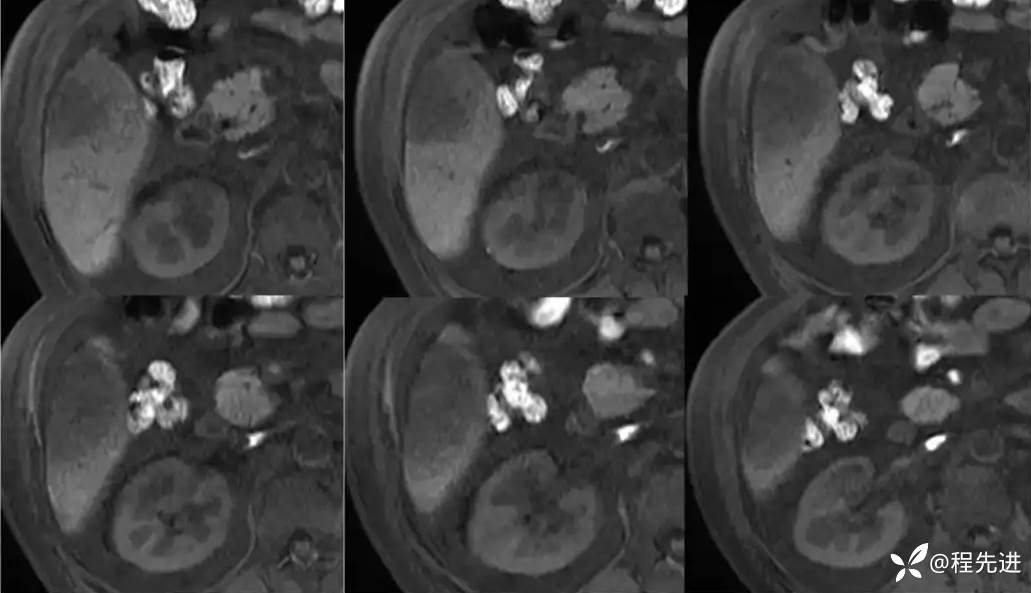

门静脉期:

移行期:

移行期冠状位:

肝胆期: